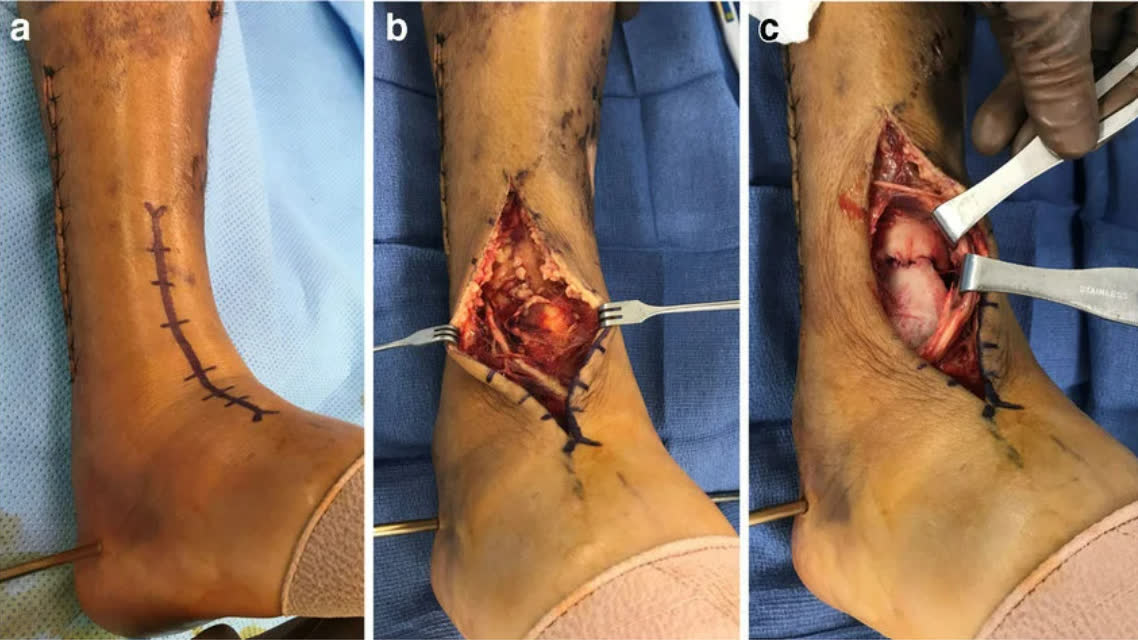

Хирургические доступы

Переднелатеральный доступ

- Показания: переднелатеральный фрагмент (Chaput/Tillaux-Chaput), переднелатеральная колонна

- Разрез между сухожилиями длинного разгибателя пальцев и латеральной лодыжкой

- Переднелатеральный фрагмент присутствует при большинстве переломов с вовлечением суставной поверхности дистального отдела большеберцовой кости [Rammelt et al., JBJS Am, 2022]

Переднемедиальный доступ

- Показания: медиальная колонна, центральная импакция суставной поверхности

- Разрез между сухожилием передней большеберцовой мышцы и медиальной лодыжкой

- Модифицированный передний дугообразный разрез в сочетании с техникой MIPO [Wu et al., BMC Musculoskelet Disord, 2020]

Заднелатеральный доступ (положение на животе)

- Показания: задняя колонна (фрагмент Volkmann), заднелатеральный вариант пилона

- Между сухожилиями малоберцовых мышц и длинного сгибателя первого пальца

- Позволяет напрямую визуализировать заднюю суставную поверхность

- Комбинация заднелатерального и заднемедиального доступов: частота раневых осложнений 6%, репозиция <1 мм ступеньки/щели в 94% случаев [Campbell et al., J Orthop Trauma, 2022]

Заднемедиальный доступ

- Показания: медиальная колонна, заднемедиальные фрагменты

- Между сухожилиями задней большеберцовой мышцы и длинного сгибателя пальцев

- Безопасно комбинируется с заднелатеральным доступом [Campbell et al., 2022]

Принципы выбора доступа

Доступ определяется стратегией репозиции, а не выбором импланта. Основа планирования — аксиальные КТ-срезы на 1 см выше суставной щели голеностопного сустава.

При полных внутрисуставных переломах (43-C) передний доступ предпочтителен в большинстве случаев при адекватном состоянии мягких тканей. Выбор между переднемедиальным и переднелатеральным определяется точкой выхода передней линии перелома на переднюю поверхность большеберцовой кости. Ориентир — передний гребень большеберцовой кости (crista tibiae):

- Линия перелома выходит медиальнее гребня (в сторону медиальной лодыжки) — переднемедиальный доступ. Обеспечивает экспозицию передней и медиальной поверхности плафона, удобен для работы с центральной импакцией. Ограничение: затруднена визуализация латерального желоба и мелких переднелатеральных фрагментов

- Линия перелома выходит латеральнее гребня (в сторону вырезки малоберцовой кости, фрагмент Chaput/Tillaux-Chaput) — переднелатеральный доступ. Обеспечивает визуализацию переднелатеральных фрагментов, синдесмоза и латерального желоба. Более щадящий для мягких тканей. Ограничение: меньшая экспозиция проксимально, часто требует дополнительного доступа

Противопоказания к переднему доступу: контаминированная рана передней поверхности голени, геморрагические фликтены, рубцы от предшествующих операций. В этих случаях задние доступы могут использоваться как основные.

| Мягкотканный покров | Умеренный | Минимальный | Хороший (мышечный) | Умеренный |

| Частота раневых осложнений | Умеренная | Наиболее высокая | Наименьшая | Низкая |